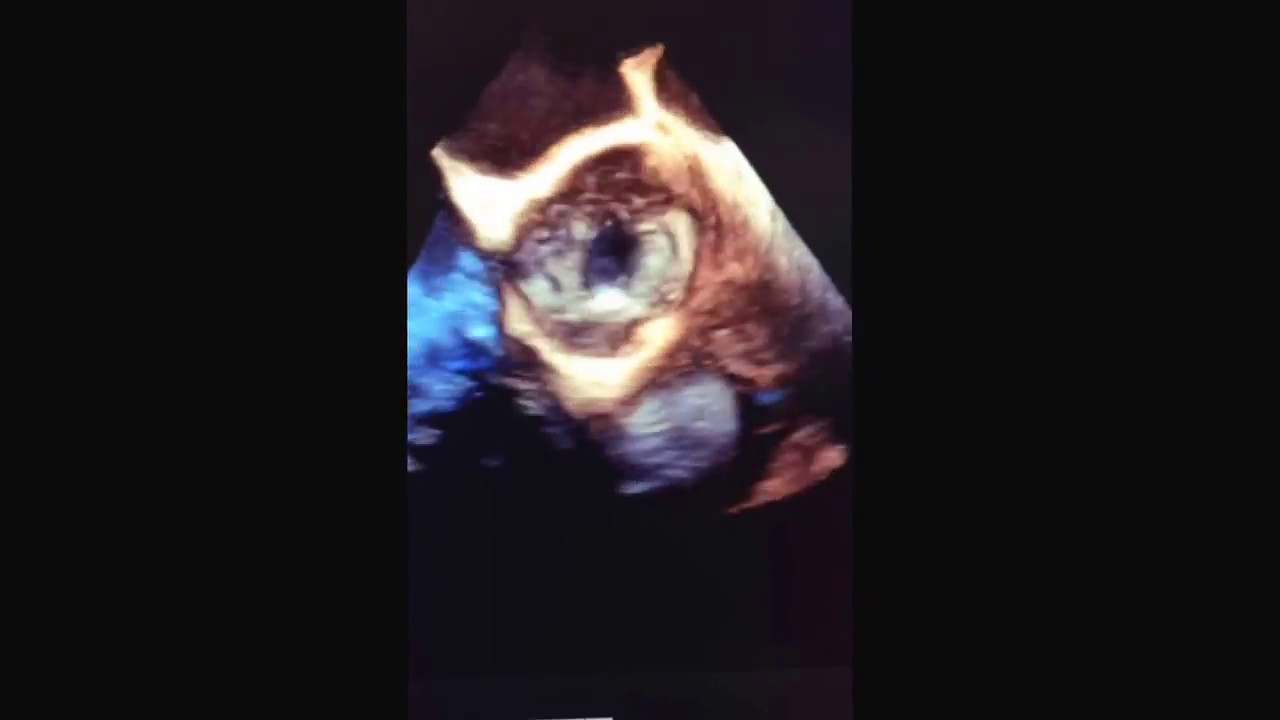

Prothèse mécanique aortique ATS échocardiographie 3D

Prothèse mécanique aortique ATS échocardiographie 3D camera iphone 8 plus apk